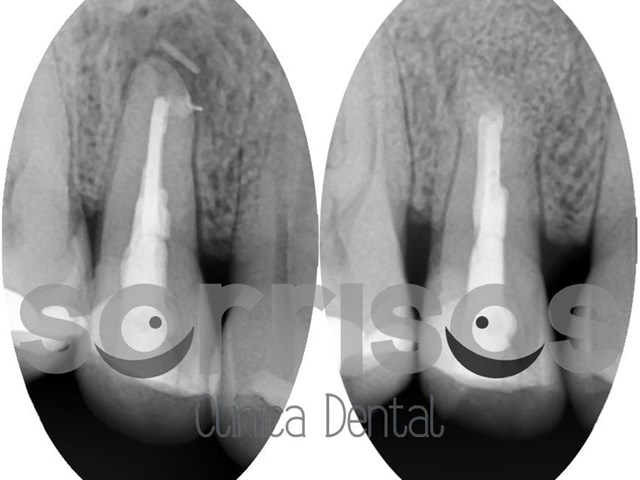

Apicectomía en el tratamiento de la infección dental. 30 sep

Apicectomía en el tratamiento de la infección dental.

Los dientes, en su interior, presentan una gran cantidad de vasos sanguíneos y nervios que conforman la pulpa dental.                En ocasiones, la irritación crónica debido a una caries o un trauma puede producir la inflamación de la pulpa, lo que se conoce como pulpitis reversible, que si no se cura con el tiempo se vuelve irreversible. La pulpitis se caracteriza por un dolor más o menos intenso que responde ante estímulos diferentes dependiendo del estadío en el que se encuent...